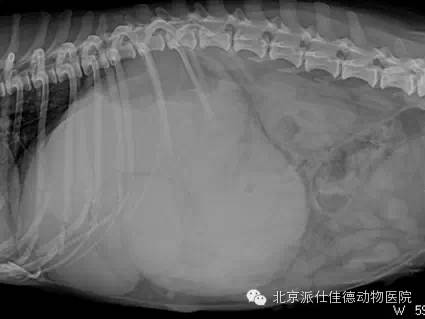

14.有些动物突然出现贫血,也没有发生外伤,腹围突然增大,经检查发现内脏大出血,最常见的是血管瘤破裂,如脾脏肿瘤破溃、肝脏肿瘤破溃、主动脉夹层瘤破裂等等。

20.有些动物表现为腹围突然增大,经检查发现大量腹水,再检查发现腹腔内多个肿瘤,并已经扩散。